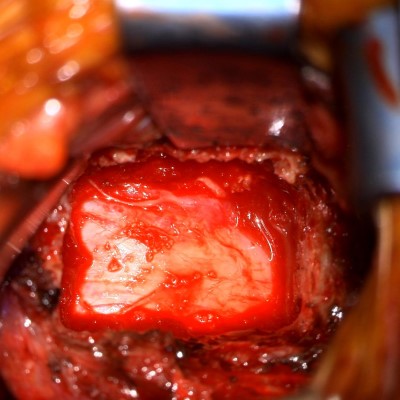

- Intra-op